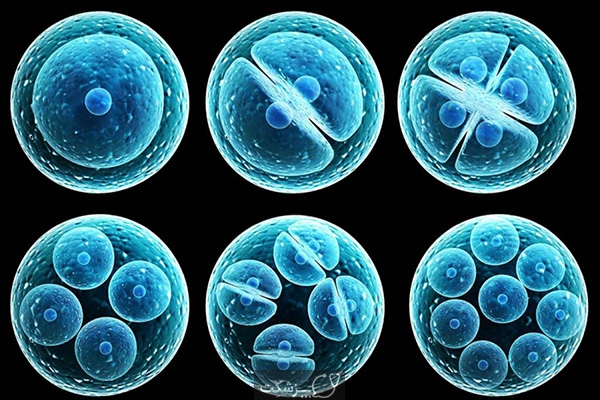

قیمت: 42٬000 تومان - دسته بندی فایل: پاورپوینتپاورپوینت سلولهای بنیادین

فروش ویژه پاورپوینت حرفه ای سلولهای بنیادین با تخفیف استثنائی 45 هزار تومان تعدا اسلاید: 16 اسلاید